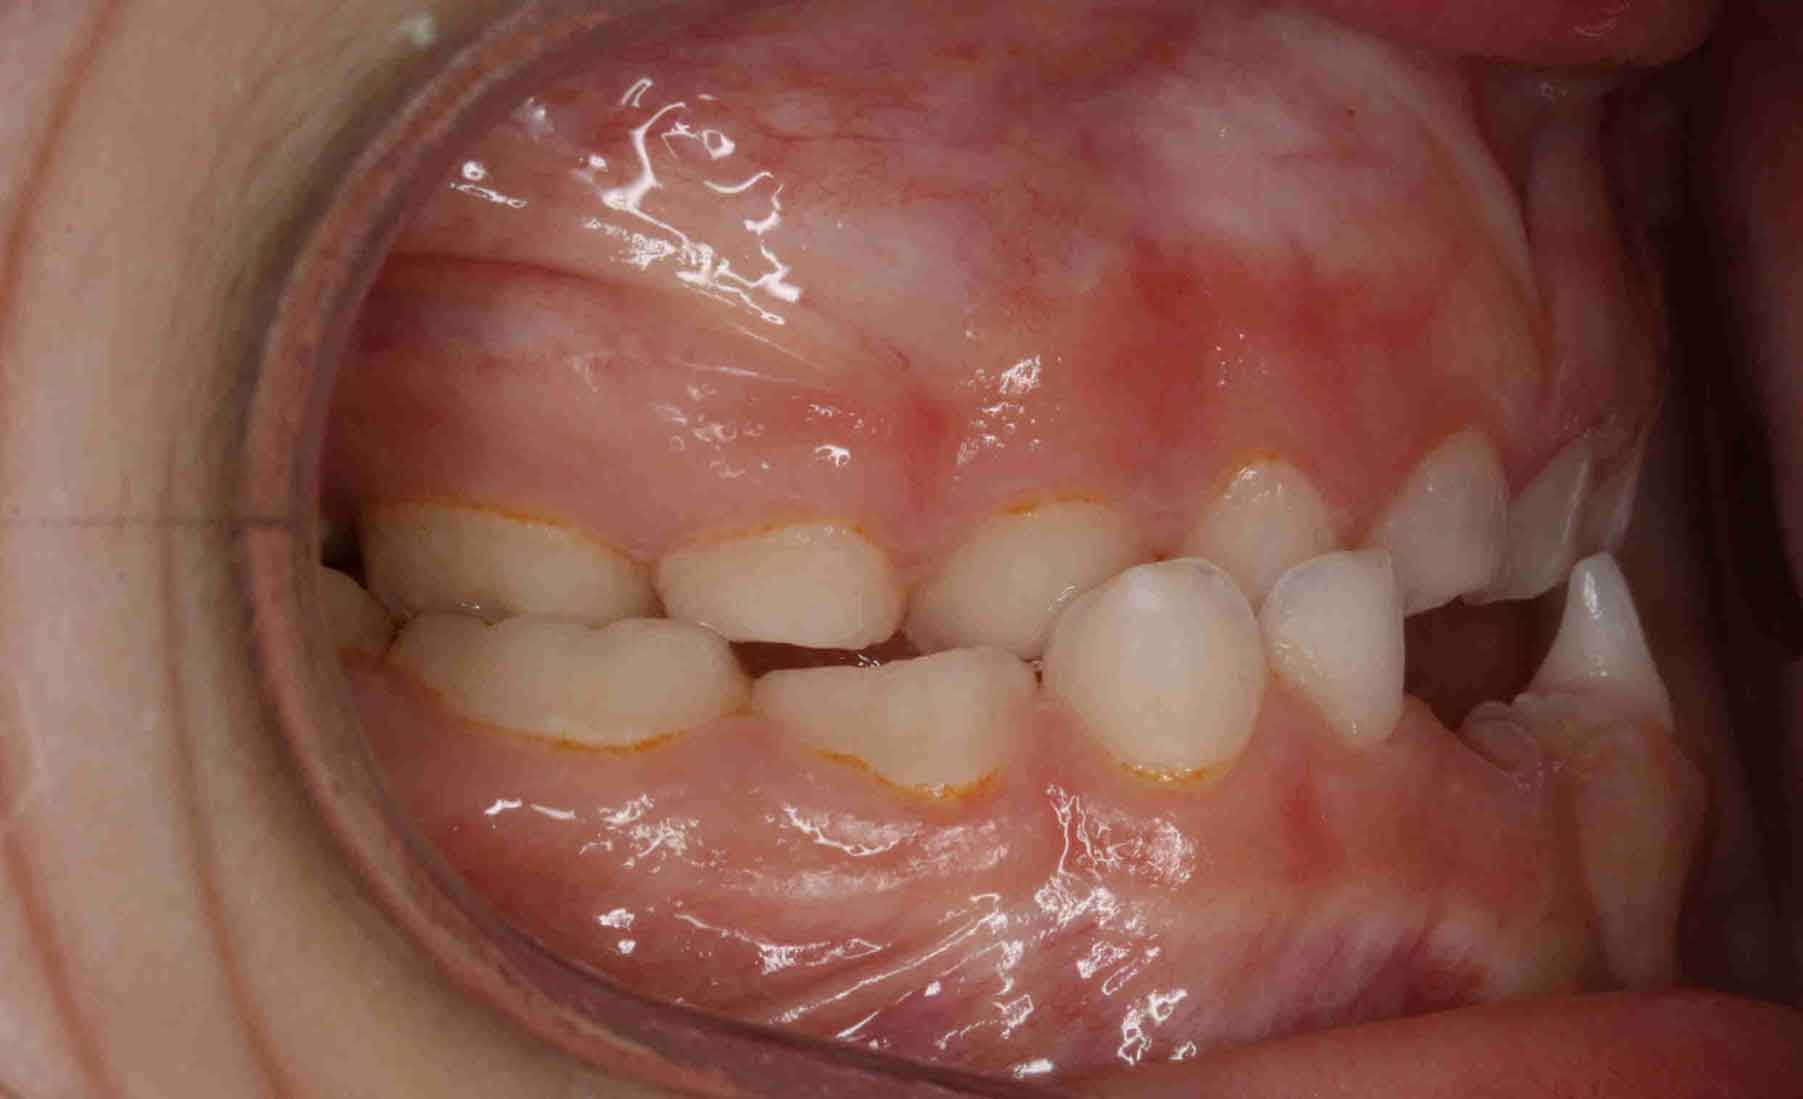

Tratamiento solo interceptivo 1ª Fase

En las siguientes imágenes puedes ver distintos resultados del tratamiento, deslizando la barra central de un lado a otro.